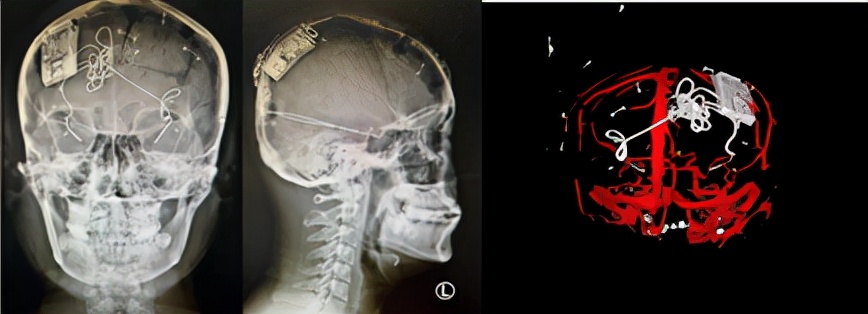

影像評估